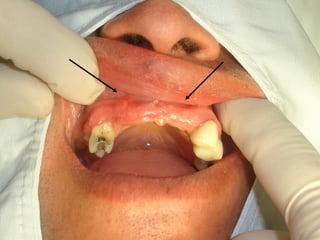

• Paciente de 25 años con

• Paciente de25 años con pérdida casi total de dientes superiores y prótesis mal adaptada. • Ganchos que no cumplen su función.